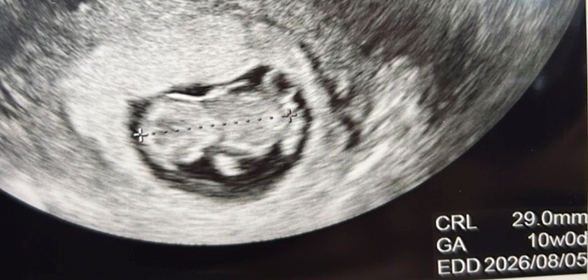

エコーに映った赤ちゃんがこちらでした。

CRLは29.0mm

機械に表示されたGA(妊娠週数)も10w0dと、週数相当にしっかり成長していました。

エコーで見えた小さな子は、手足をバタバタと動かし、とても元気な様子だったみたい。

羊水にぷかぷか浮かびながらバタバタする我が子に、先生も笑っていたそうです。